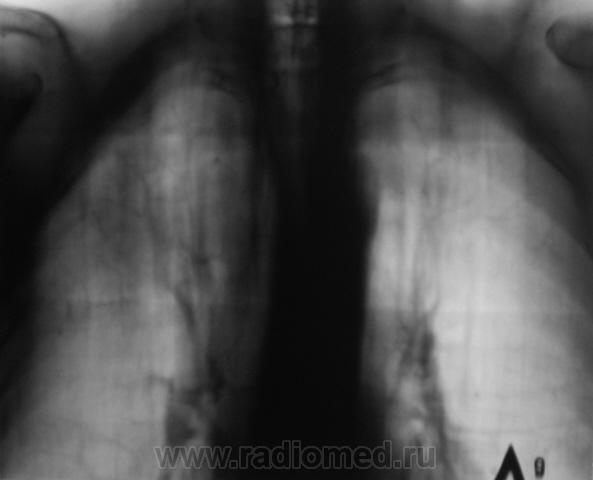

И откуда он берется? Очередной контроль после флюорографии.

Контроль передвижного флюорографа.

Сегодня дообследовали.

да тубркулеза у Вас хватает!

Но может оказаться и пневмонией..

Не оказался "пневмонией". Сегодня пришел коллега фтизиатр записать изображения на диск, посылает пациента в ОПТД, палки найдены.